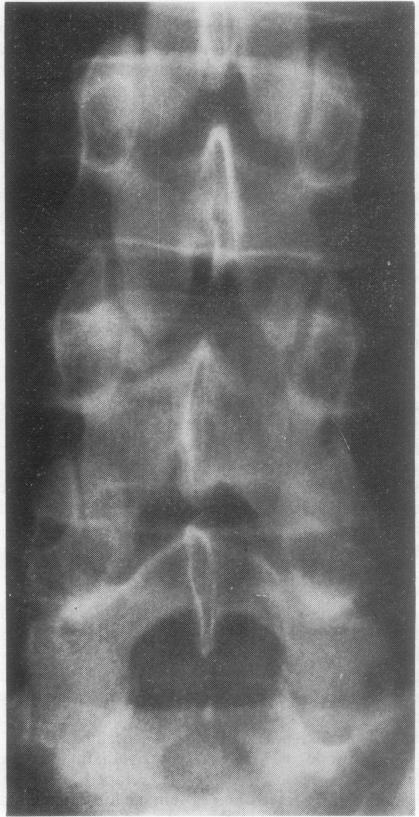

背痛患者中的小脊柱骨折。

Small spinal fractures in back pain patients.

Small fractures in the posterior elements of the spine were identified by stereoscopic radiography in 7 patients suffering from back pain. The clinical data on these 7 patients are presented.

通过立体放射摄影术,在7名背痛患者中发现了脊柱后部结构的小骨折。本文呈现了这7名患者的临床资料。